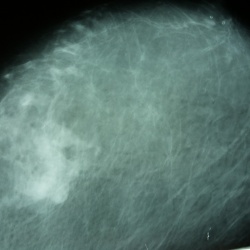

Смущает верхний квадрант левой молочной железы

Фкм?42 года на 7 день цикла.Прошу поделиться мнениями,заранее извините за снимки-учимся(маммограф "viola")-снимал на планшет.